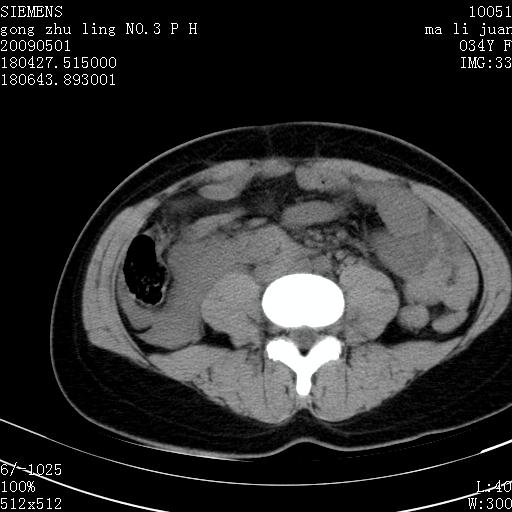

标题: CT19733:右肾碎裂

青年女性,骑摩托车摔伤。

右肾破裂并右侧腹膜后间隙出血。

右肾破裂伴肾包膜下及肾周血肿。

支持 右肾破裂伴肾包膜下及肾周血肿